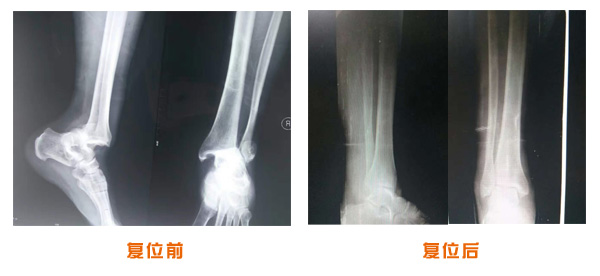

肥城市安駕莊梁氏骨科醫(yī)院是一所以梁氏手法正骨配合膏藥為特色的現(xiàn)代化專(zhuān)科醫(yī)院。

梁氏骨科術(shù)始創(chuàng)于清雍正年間,歷經(jīng)八代,至今已有三百年歷史。據(jù)1929年泰安縣志載“梁瑞圖先生,字增生,號(hào)蓮峰,安駕莊人,精岐黃并發(fā)明接骨,凡跌打車(chē)凡跌打車(chē)軋皮不破而碎骨者......【詳細(xì)】 |